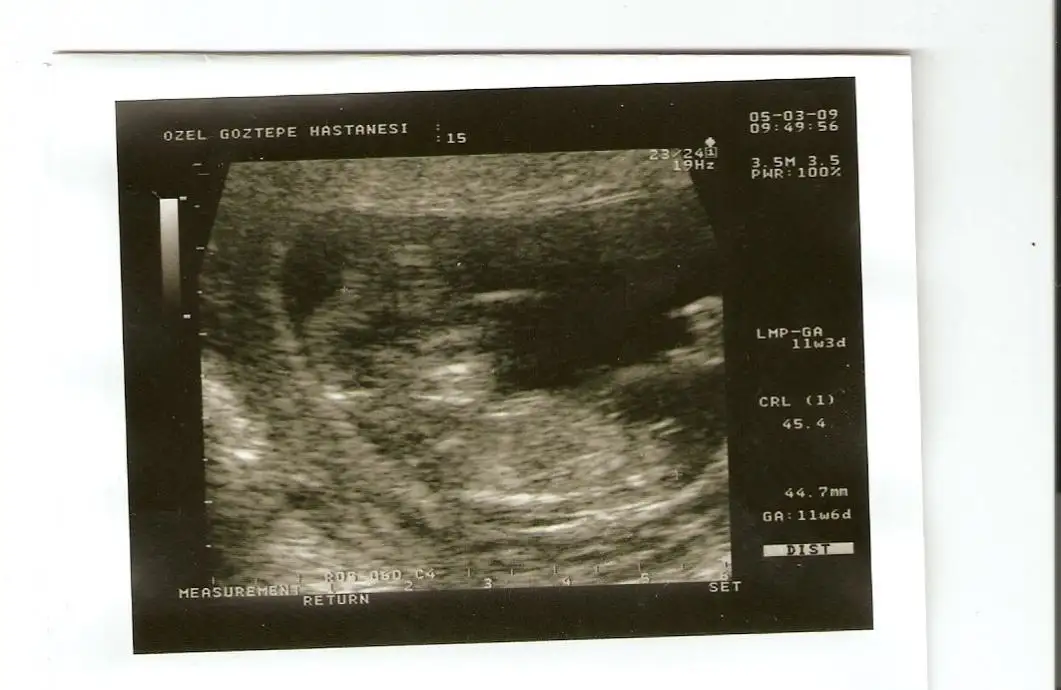

kızlar birdaha yükledim. bu sefer işaretledim ama parmaklarla karışmasın:)kaydirigubbakcemile3

canim yaa bence o bebisin eli.kol kemigini takip et bak bi..hayirlisi olsun insallah.bana eliymis gibi geldi.CADIARZUcünkü o kadar büyük olmuyo benimde oglum olcak hayirlisiyla ordan biliyorum azicik yani.